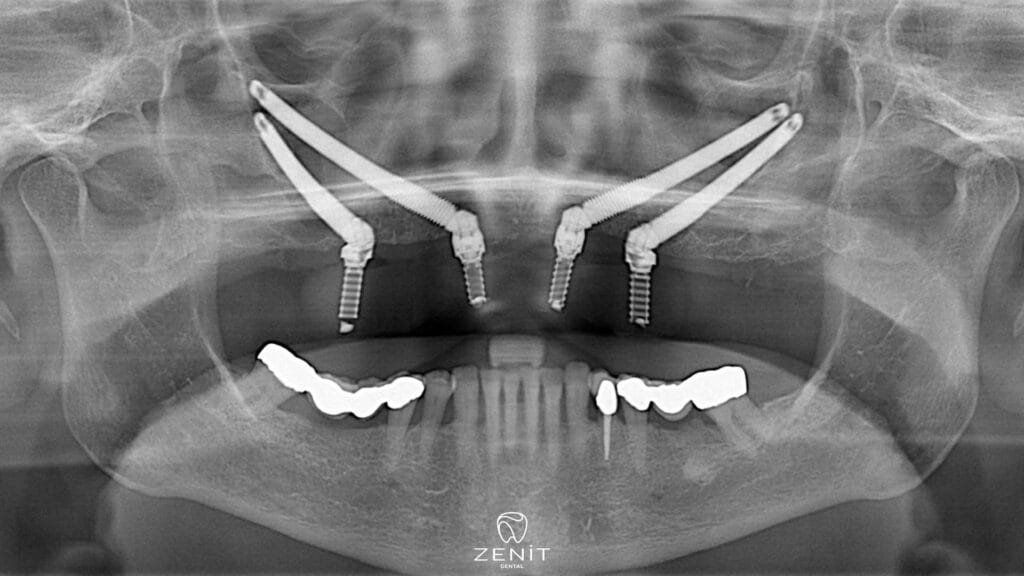

Zygoma implants offer an excellent alternative for patients with inadequate jawbone and provide a revolutionary treatment in the facial area. These special implants, unlike traditional implants, are placed in the zygomatic (zygoma) bone instead of the upper jaw bone. Since the zygomatic bone has a denser and stronger structure than the jawbone, zygoma implants can be safely placed in this area. Thanks to zygoma implants, even patients with advanced bone loss can achieve aesthetically and functionally satisfactory results.

Zygoma implants placed in the cheekbone, unlike other dental implants, are placed not in the jawbone, but in the area called zygomatic bone, which is located in the middle of the face and has a very solid structure. The zygomatic bone has a denser structure than other bones and bone loss usually does not occur. Thanks to this feature, zygoma implants offer a safe and effective solution to patients with jaw bone deficiency.

Zygomatic implant treatment is a complex procedure performed by an experienced surgeon. The procedure is usually done under general anesthesia and can take several hours. Application of zygomatic implants includes the following steps:

- Evaluation and Planning: The first step is to undergo a detailed evaluation of the patient. The condition of the jaw and facial bones is analyzed using advanced imaging techniques such as dental tomography.

- Implant Placement: Zygoma implants are placed in the cheekbone instead of the upper jawbone. The surgeon works with high precision when placing the implants, because reaching the zygomatic area and placing the implants in the correct position requires great care.